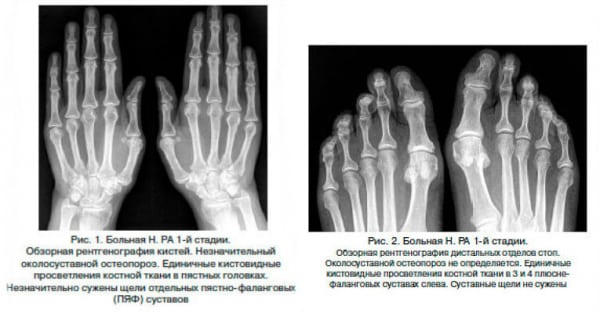

Для диагностирования ревматоидного артрита проводятся инструментальные и биохимические исследования. Наиболее информативна рентгенография, результаты которой позволяют оценить степень поражения соединительнотканных и костных структур. Консервативное лечение заключается в длительном курсовом приеме препаратов различных клинико-фармакологических групп. При прогрессировании патологии требуется хирургическое восстановление суставов.

С помощью пункции производится забор суставной жидкости для исследования ее состава. На раннем этапе развития патологии информативно УЗИ, позволяющее выявить даже незначительные деструктивные изменения в соединительнотканных структурах. Обязательно проводится рентгенологическое исследование. На полученных изображениях отчетливо визуализированы признаки остеопороза (снижения костной массы), эрозии, сращения суставных щелей. Рентгенография помогает дифференцировать ревматоидный артрит от подагры, остеоартрита, артроза, инфекционных воспалений суставов. В диагностике могут быть использованы денситометрия, сцинтиграфия, артроскопия, биопсия подкожных образований.